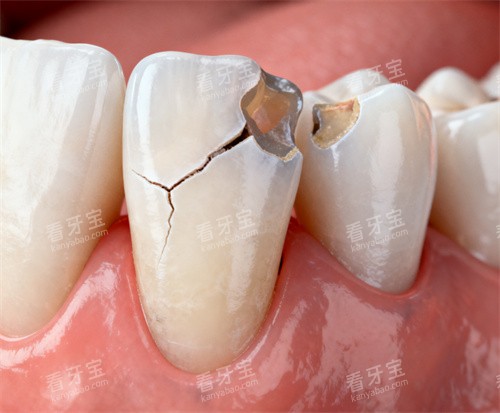

牙周治疗:从“救牙”到“保牙”

诊疗流程:先通过牙周探诊、影像学检查评估牙周破坏程度,再制定个性化治疗方案(如龈上洁治、龈下刮治、牙周手术)。

特色服务:提供“牙周维护套餐”,术后每3个月免费复查,预防疾病复发。